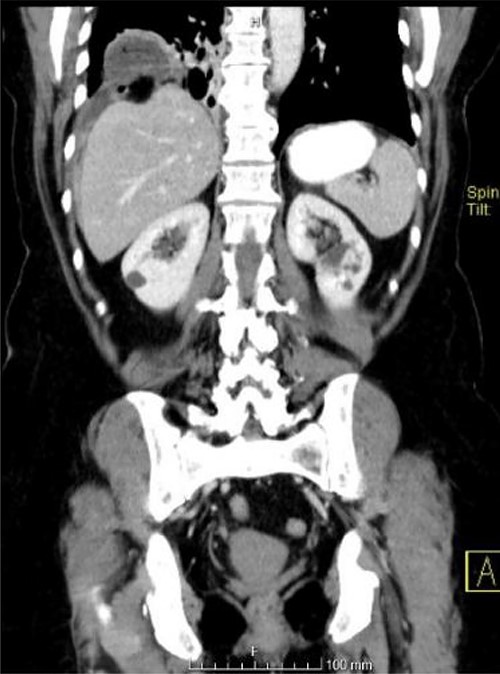

An abdominal computed tomography (CT) scan was performed, which identified an internal hernia at the root of the right mesentery, an apparent abscess in the right lung base (65 × 55 mm) (Fig. 1) as well as elevation of the right diaphragmatic hemi-dome with Chilaiditi sign (Fig. 2).